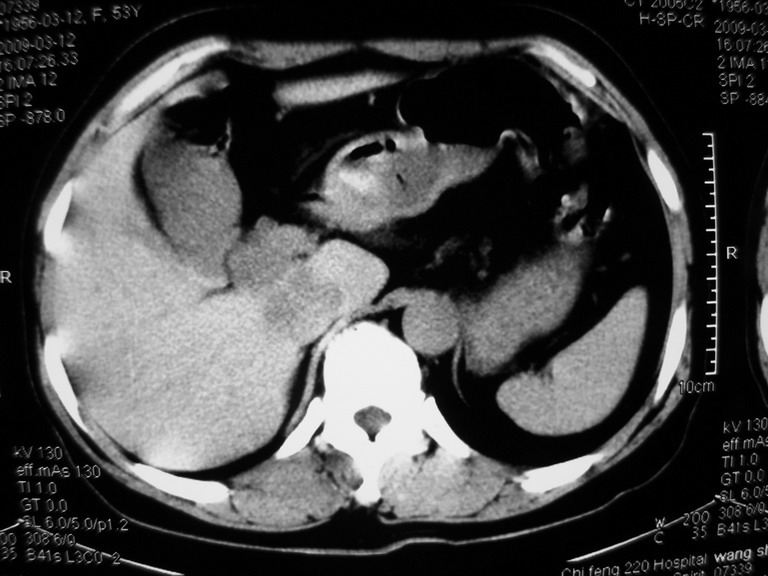

患者,女性50岁,上腹部不适2年余,既往多次腹部彩超未见异常,今日上午在我院查彩超发现肝右叶囊实性病变,外院辅助检查,afp,cea,ca199, 都在正常范围内,无肝炎史否认肿瘤史,生活在牧区

接着往下一贴看,有静脉期和延迟期,在看看和下腔静脉及十二指肠的关系,腔静脉内是不是栓子?

考虑肝右叶与尾叶交界区肝癌(部分外生),侵犯下腔静脉并下腔静脉瘤栓形成。